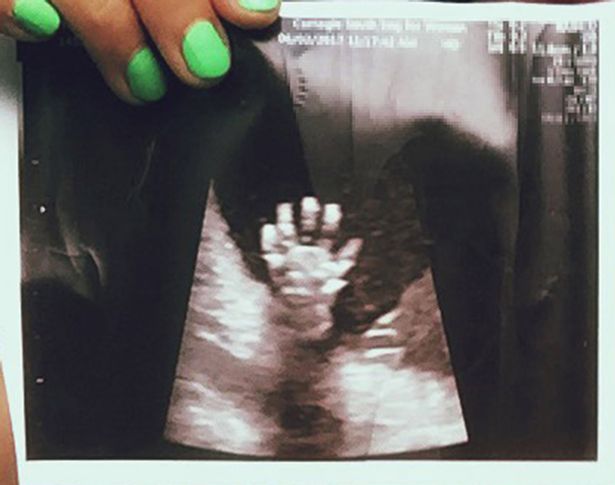

Old  Default Mẹ kinh ngạc thấy con giơ tay “high-five” trong lúc siêu âm

Vietbf.com - Bà mẹ kinh ngạc khi xem bức ảnh siêu âm bầu thai của mình 20 tuần, lại thấy con giơ 5 ngón tay hình như muốn “high-five” (đập tay) với mẹ, khiến cặp vợ chồng đăng bức ảnh này lên mạng xã hội và nó lan truyền thật nhanh chóng.

Libby cầm bức ảnh siêu âm lúc mang thai 20 tuần

Trong lần siêu âm ở tuần thứ 20, cặp đôi vô cùng ngạc nhiên khi nhìn thấy con gái giơ cả bàn tay lên, xòe ra 5 ngón. Cặp vợ chồng đăng bức ảnh này lên mạng xã hội và nó lan truyền nhanh chóng, theo Mirror.

Bé gái giơ cả bàn tay lên, xòe ra 5 ngón

Libby, hiện đang mang thai 30 tuần, cho biết: "Bức ảnh được chia sẻ bởi rất nhiều người mang thai trên Instagram. Lần cuối tôi kiểm tra nó có 6.000 lượt thích, vì vậy tôi đoán đó là một hiện tượng, tôi cũng có rất nhiều bình luận về bức ảnh".